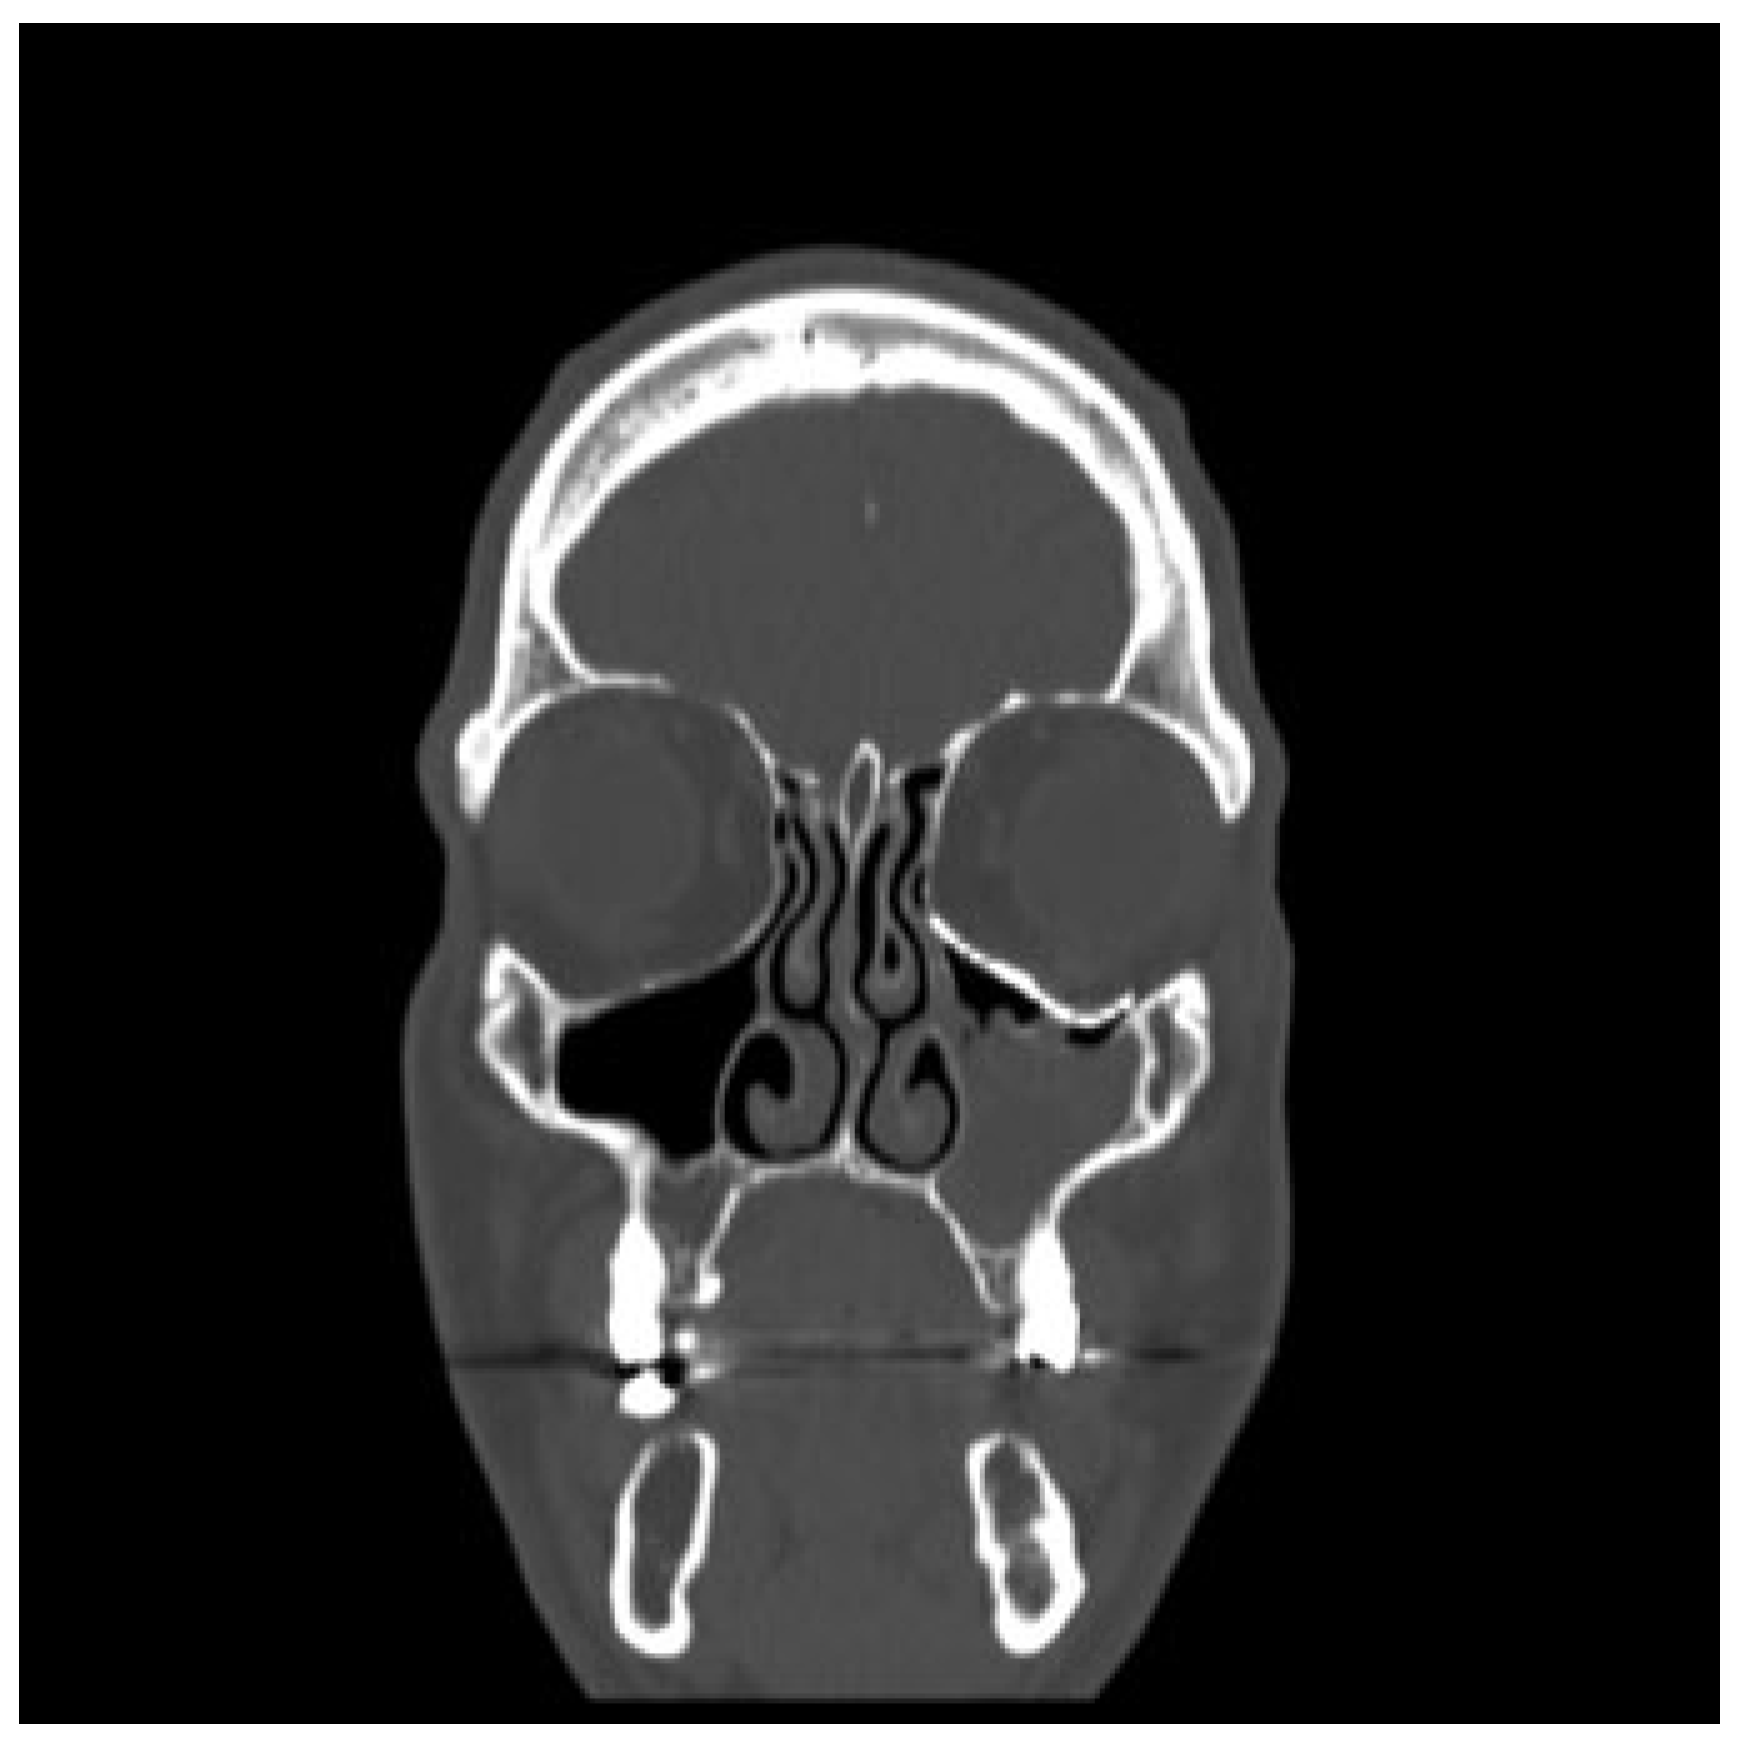

Figure 2. Case 1: Mirrored contralateral orbit (blue) overlying the left side orbital floor defect, extending medially in a hinge-door fashion.

A 12-year-old boy presented with a left orbital floor defect extending into the medial wall due to a traffic accident that occurred 1 month earlier. After rendering of the high-resolution CT DICOM data, mirroring was performed using Mimics Innovation Suite (Materialise, Heverlee, Belgium), which showed extension of the dislocation into the medial wall (►Figure 2). Two interlocking porous pieces were designed for transconjunctival insertion (►Figure 3). The surgery was performed 3 months after the accident. Screw position was determined after taking into account infraorbital nerve position and bone thickness. Microscrews (1.2-mm diameter; Surgi-Tec, Sint-Denijs-Westrem, Belgium) were used for plate fixation. The pieces did not overlap vertically, resulting in unfavorable rotational movement around the sagittal axis upon insertion (►Figure 4). Two months postoperatively, there was normal ocular motility, no enophthalmos, and no V2 disturbance.